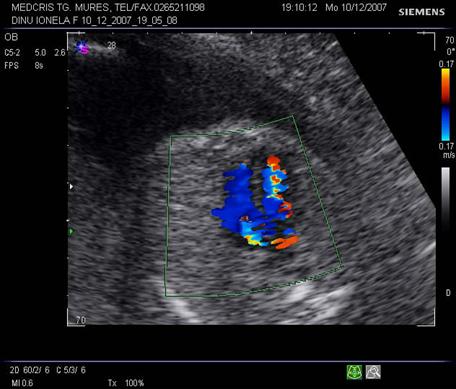

Fig. nr 183. La examenul Doppler, se poate stabili integritatea septului ventricular, in sectiunea cord in 4 camere